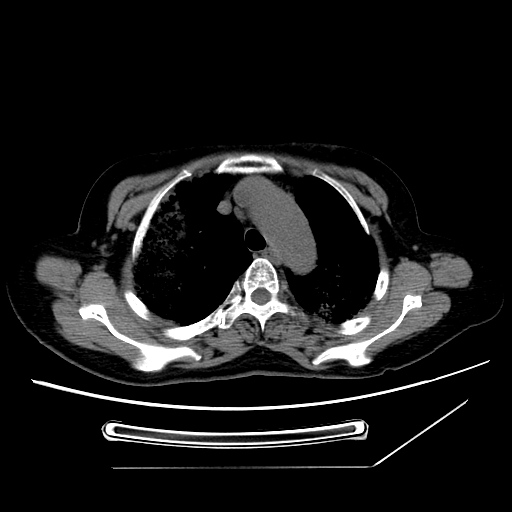

标题: CT25393:病人45岁,咳嗽,吐黄痰带血丝,发热,胸闷月余 [打印本页]

标题: CT25393:病人45岁,咳嗽,吐黄痰带血丝,发热,胸闷月余

1、左肺中央型肺癌并双肺弥漫性转移   2、双肺部感染    3、肺大泡     4、左侧胸腔积液

双侧肺弥漫性病变,可见“空泡征”及“蜂窝征”,考虑肺泡癌可能性大,左侧胸腔积液,考虑胸膜受累可能!

1)不排除肺泡癌可能。2)左侧胸腔积液。